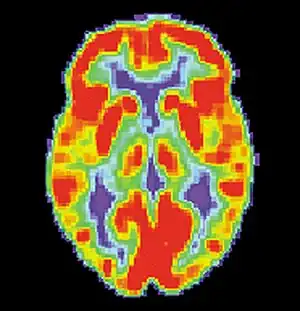

Alzheimer's disease

Alzheimer's disease (AD) is a progressive, degenerative and fatal brain disease, in which cell to cell connections in the brain are lost. Alzheimer's disease is the most common form of dementia.[2] Globally approximately 1–5% of the population is affected by Alzheimer's disease.[3] Women are disproportionately affected by Alzheimer's disease. The evidence suggests that women with AD display more severe cognitive impairment relative to age-matched males with AD, as well as a more rapid rate of cognitive decline.[4]

Aging

Normal aging, although not responsible for causing memory disorders, is associated with a decline in cognitive and neural systems including memory (long-term and working memory). Many factors such as genetics and neural degeneration have a part in causing memory disorders. In order to diagnose Alzheimer's disease and dementia early, researchers are trying to find biological markers that can predict these diseases in younger adults. One such marker is a beta-amyloid deposit which is a protein that deposits on the brain as we age. Although 20-33% of healthy elderly adults have these deposits, they are increased in elderly with diagnosed Alzheimer's disease and dementia.[35]

Amyloid plaques associated with Alzheimer's disease that increase in number with age

As seen in the examples above, although memory does degenerate with age, it is not always classified as a memory disorder. The difference in memory between normal aging and a memory disorder is the amount of beta-amyloid deposits, hippocampal neurofibrillary tangles, or amyloid plaques in the cortex. If there is an increased amount, memory connections become blocked, memory functions decrease much more than what is normal for that age and a memory disorder is diagnosed.[35][37]